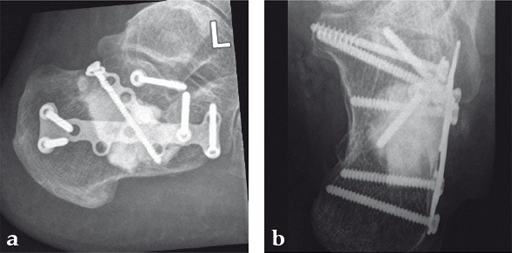

Case 1: A 70-year-old man sustained a Sanders IIA fracture of his left calcaneus.

(Case provided by Michiel Verhofstad, Tilburg, The Netherlands)

After open reduction a gap was left due to impaction of the osteoporotic metaphyseal bone. To support preliminary maintenance of the primary reduction a block of calcium phosphate was introduced beneath the posterior facet. The rest of the gap was filled with Norian drillable. After hardening plate osteosynthesis was performed. Two screws were placed through the fiber-enhanced calcium phosphate. Weight bearing was started 6 weeks later. After 6 months the fracture was healed without secondary loss of reduction. Note that at that time the degradation of the void filler is visible.